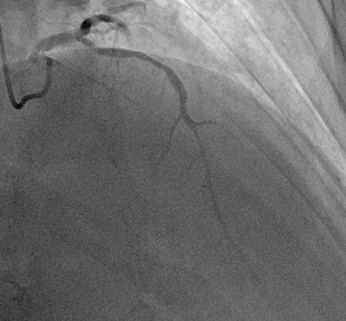

Los hallazgos fueron los siguientes:

· Tronco coronario izquierdo sin lesiones angiográficas significativas; descendente anterior (DA) estenosis severa entre tercio proximal y medio, suboclusiva; estenosis tercio distal coronaría derecha sin lesiones angiográficas significativas. (Ilustración 3 y 4).

Ilustración 4 Arteriografía coronaria izquierda, lesiones en arteria descendente anterior

Fuente: Hospital de Especialidades Guayaquil “Doctor Abel Gilbert Pontón”.

Se decidió realizar angioplastia coronaria percutánea a la DA colocándose 2 stent medicado 3 x 20 mm en tercio proximal y medio (Ilustración 5)

No hubo complicaciones durante el procedimiento.

Ilustración 5 Angioplastia con stent en descendente anterior.